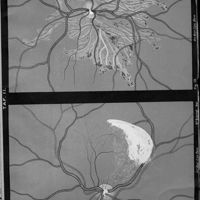

Ophthalmoskopische Studien

- Ophthalmoskopische Studien

- Mitteilungen aus kliniken und medicinischen Instituten der Schweiz, Vol. 3, pp. 545-82

- Siegrist - Hutchinson (syndrome de)